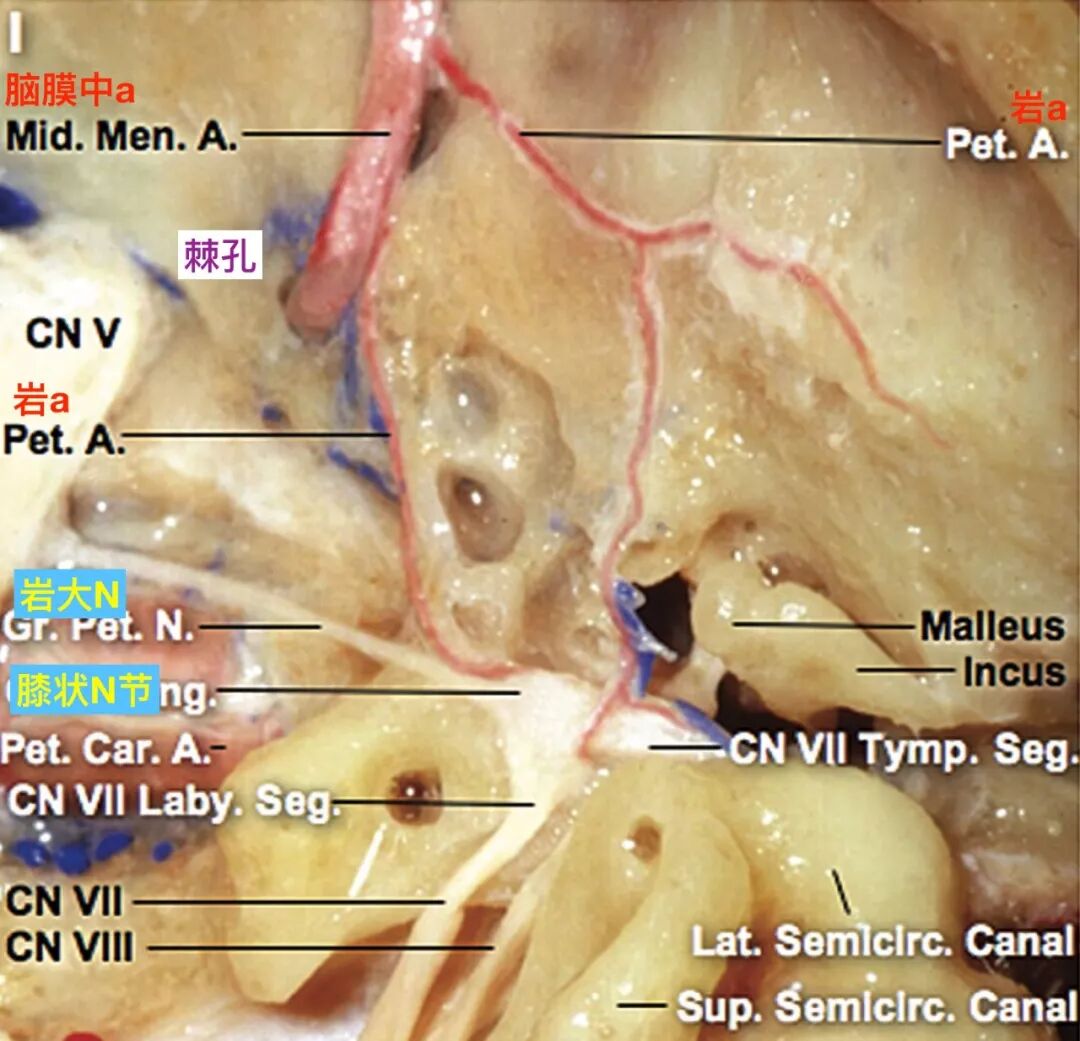

单支岩动脉通过岩大神经裂孔。岩动脉到达面神经后,发出小分支沿膝状神经节和面神经鼓室段走行,另一支沿岩大神经走行。鼓室内的砧骨(incus)和锤骨(malleus),以及半规管显露(El-Khouly 2008)。

![]()